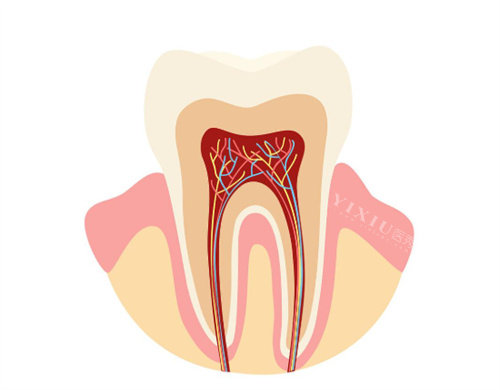

根管治疗:680 元起